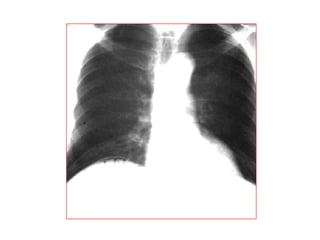

 Phim buïng khoâng chuaån bò: xem möïc nöôùc hôi

baát thöôøng, hôi töï do...

 Phim ôû tö theá naèm ngöõa, naèm nghieâng, naèm

doác 45ñoä..

 Phim ngöïc ñöùng thaúng: tìm lieàm hôi töï do

döôùi cô hoaønh, beänh lí ñaùy phoåi..

THUÛNG TAÏNG ROÃNG

* Vò trí

o Thöôøng ôû phaàn cao oáng tieâu hoaù (vieâm loeùt, nhieãm truøng,

thuûng do ngoaïi vaät nuoát vaøo…)

o Caùc oáng tieâu hoaù tröôùc coät soáng (chaán thöông)

* Daáu hieäu kinh ñieån: lieàm hôi döôùi hoaønh: xuaát hieän 6-8

giôø sau thuûng vôùi löôïng hôi khoaûng 20-50ml

* Caùc tö theá khaùc: BN nghieâng (T) laáy heát bôø ngoaøi gan vaø

hoá chaäu (P), naèm ngöõa tia phoùng ngang…

Chẩn đoán phân biệt liềm hơi dưới hoành:

-Túi hơi dạ dày

-Mô phổi bình thường nằm giữa đáy phổi và cung sườn sát

trên với đáy phổi

-Hội chứng Chilaiditi